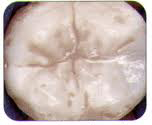

Chewing surface before sealant

Tooth protected by shaded sealant

Dental sealants are a thin resin coating that is applied to fill in narrow grooves in a tooth that has deep chewing surfaces. In some cases, the tooth structure has fine grooves or pits which accumulate plaque, not because the person doesn't brush, but because they're too narrow to allow even one bristle into them. These will develop cavities over time if not taken care of. So in order to prevent decay, the plastic coating is placed and cured making it possible to brush off all the plaque and keep your teeth healthy.